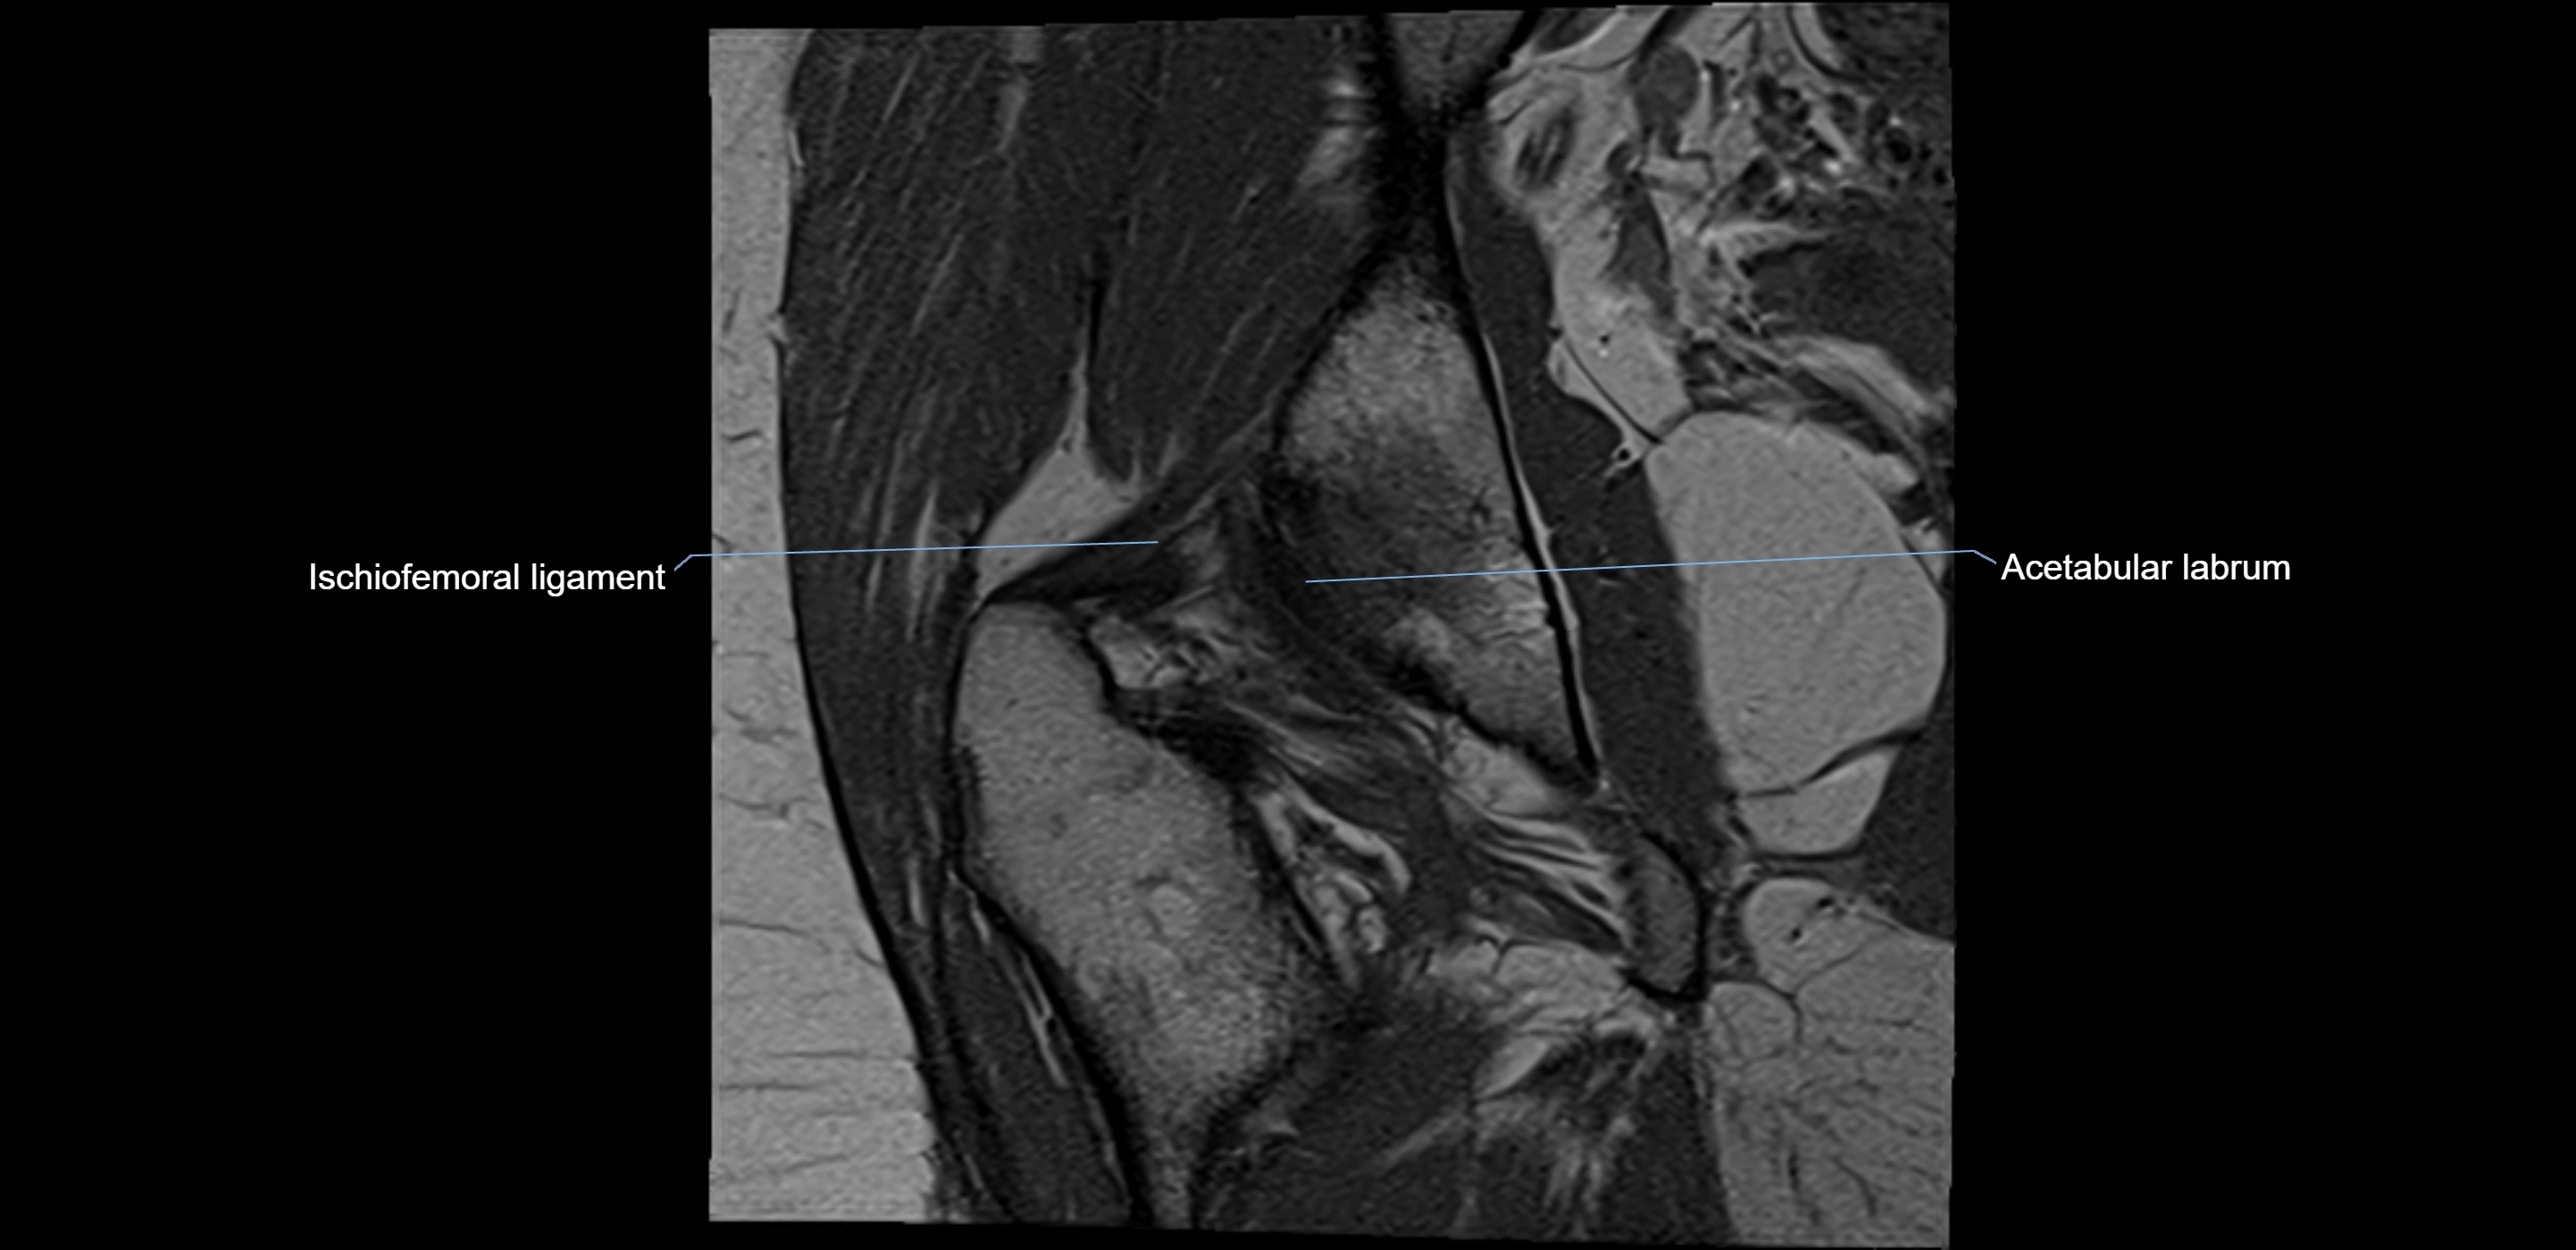

The acetabular labrum is a fibrocartilaginous ring that surrounds the rim of the acetabulum in the hip joint. It deepens the hip socket, increases joint stability, and maintains a suction seal that preserves negative intra-articular pressure. Structurally, the labrum transitions from hyaline cartilage of the acetabulum to dense fibrocartilage at its free edge.

It is triangular in cross-section, with its base attached to the acetabular rim and its apex projecting toward the femoral head. The labrum is most robust superiorly and anteriorly, where load bearing is greatest, and relatively thinner inferiorly.

Structure and Relations

• Lateral: hip joint capsule

MRI Appearance

T1-weighted images:

• Labrum: low signal intensity (dark)

• Surrounded by intermediate signal joint fluid (bright on arthrogram)

• Tears: linear or focal areas of intermediate-to-high signal interrupting labral continuity

T2-weighted images:

• Joint fluid: bright, making labral tears visible as fluid extending into or around labrum

• Degeneration: may show areas of increased signal within labrum